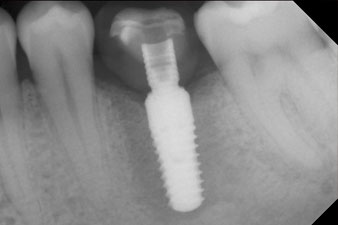

След зарастване на меките тъкани, стабилността на импланта е измерена отново преди протетичното възстановяване.

И двете стойности са практически непроменени и са между средния и високия диапазон, където по-ниската стойност винаги се използва като референтна стойност, която определя лечението.

Следователно, успешната остеоинтеграция и адекватната биологична стабилност могат да бъдат записани, което даде възможност да се вземе отпечатък в една и съща сесия.